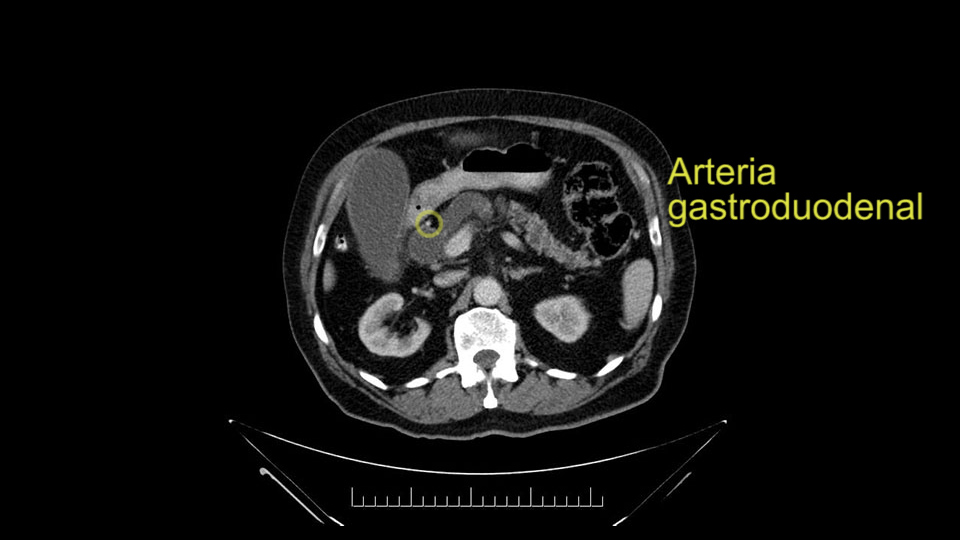

The gastroduodenal artery, a major artery that we have to divide, along with some pancreatoduodenal arteries, may have atherosclerotic changes so they would have to be handled with care, when I attempt what I think would be a pylorus-preserving pancreatoduodenectomy would be the plan. In some cases, I might make an intraoperative change and do a partial antrectomy or a pylorus-resecting Whipple, should the need arise for technical reasons but not because of the size of the tumor.

The other slowing down moment would be the gastroduodenal artery. Confirming that the gastroduodenal artery is not a dominant artery supplying blood to the liver. Liver failure is something which we don’t want due to altered blood supply to the liver or hampered arterial blood supply to the liver. So I would dissect out the hepatic artery, the left and right branches very clearly. Put a bulldog clamp on the gastroduodenal artery, make sure that the perfusion of the liver is excellent on the right and left side, and then divide the gastroduodenal artery. I would avoid using crushing instruments or crushing clamps on the gastroduodenal artery because they have a tendency to shatter in patients who are old with friable vessels so you have to be careful and tackle it with the help of a 5-0 or a 6-0 prolene sutures. In younger patients, I would just apply clips and move on when it comes to dividing the gastroduodenal artery.

First, the stenosis of the celiac trunk, which can be caused by arteriosclerosis, especially in a patient who is 83, or in patients who have arcuate ligament; we do see it, sometimes in much younger patients. In those cases, it may be that the circulation of the hepatic artery comes entirely from the gastroduodenal artery and its anastomoses, through the pancreaticoduodenal arteries, coming from the superior mesenteric artery. This means that before the gastroduodenal artery is ligated, we first clamp and wait 30 seconds to a minute, to feel and check the arterial inflow to the liver. If the pulse is diminished or there is a complete absence of the pulse, the surgery should be modified or probably a pancreatoduodenectomy cannot be done, because of the risk - when ligating the gastroduodenal artery - of causing fulminant hepatic ischemia postoperatively.

I am a believer in pylorus preservation. And in this case I see no reason why that wouldn't be possible. Mobilize the duodenum, divide the gastroepiploic vessels and divide the duodenum. I try to divide it with a linear stapler about four centimeters from the pylorus to have adequate length for my GI anastomosis. This facilitates exposure of the head neck of the pancreas. I find the gastroduodenal artery. This patient has normal arterial anatomy. Always on every preoperative CT scan I look to see if there is a replaced right hepatic. In this case I did not see one. Regardless of how confident I am I always look carefully for variant anatomy. I always do a clamp test on the GDA before ligation. I doubly ligate the GDA with not just a tie but a suture ligature because of the risk of GDA blowout in patients with a leak.